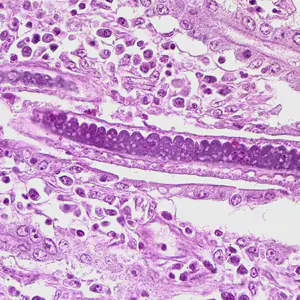

The adults of Capillaria philippinensis are very small (males: 2.3 to 3.2mm; females: 2.5 to 4.3 mm) and reside in the human small intestine, where they burrow in the mucosa

. In addition to the unembryonated, shelled eggs which pass into the environment, the females can also produce eggs lacking shells (possessing only a vitelline membrane)

, which become embryonated within the female’s uterus or in the intestine. The released larvae can re-invade the intestinal mucosa and cause internal autoinfection

. This process may lead to hyperinfection (a massive number of adult worms).

Capillaria philippinensis adult males are 2.0—3.5 mm in length and females are 2.5—4.5 mm in length. Females may contain embryonated or unembryonated eggs in utero.

The specific diagnosis of C. philippinensis is established by finding eggs, larvae and/or adult worms in the stool or in intestinal biopsies. Unembryonated eggs are the typical stage found in the feces. In severe infections, embryonated eggs, larvae, and even adult worms can be found in the feces. No valid serologic testing is available for diagnosis.